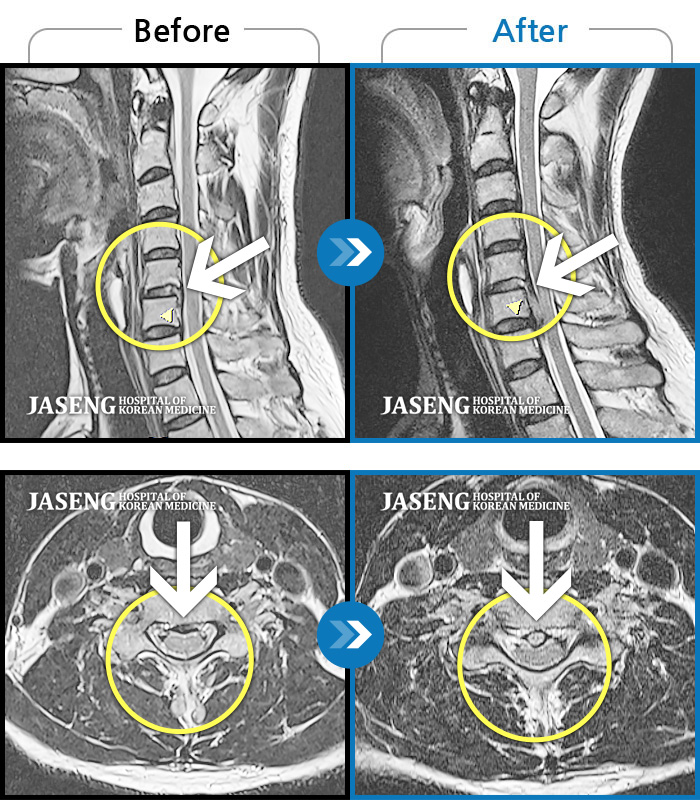

목 통증과 새끼 손가락 저림 및 안정시에도 우측 어깨 통증 호소하여 내원하셨습니다.

2022.08.10 ~ 2024.11.08